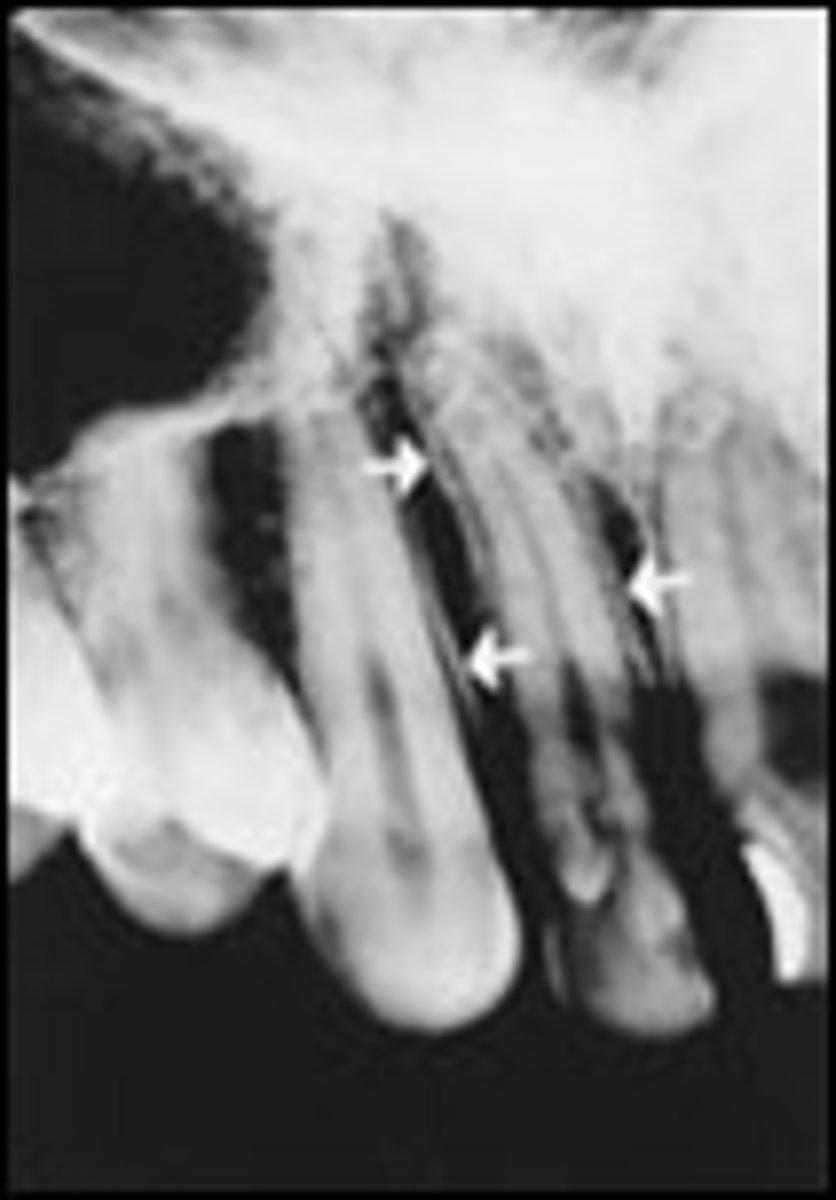

Mandibular canal

What is the radiolucent structure seen here?

Nutrient canals